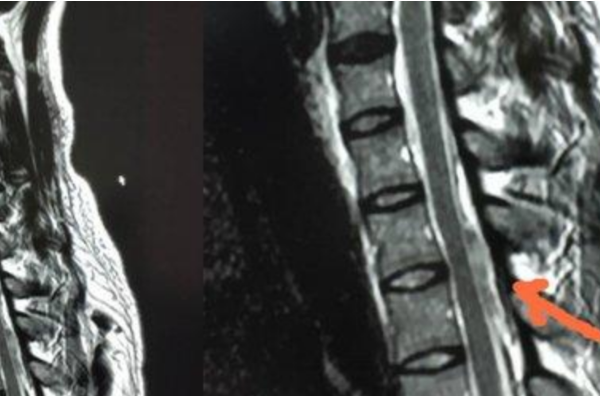

医生说小伙患的是自发的脊髓硬膜外血肿(SSEH),这是一种非常罕见的却能致残的疾病,而且每10万人中就有0.1%的人患有这种疾病,并且对于这种疾病的成因也是不得而已,所以倘若是患上此病的话,是需要尽快对脊髓进行减压和清除血肿的。

所以小伙子做了俯卧撑后出现身体方面的疼痛险些遭遇截肢的原因,正是因为他患上了非常罕见的且能致残的自发的脊髓硬膜外血肿,不过好在小伙因为救治及时,所以也在逐步恢复正常中。